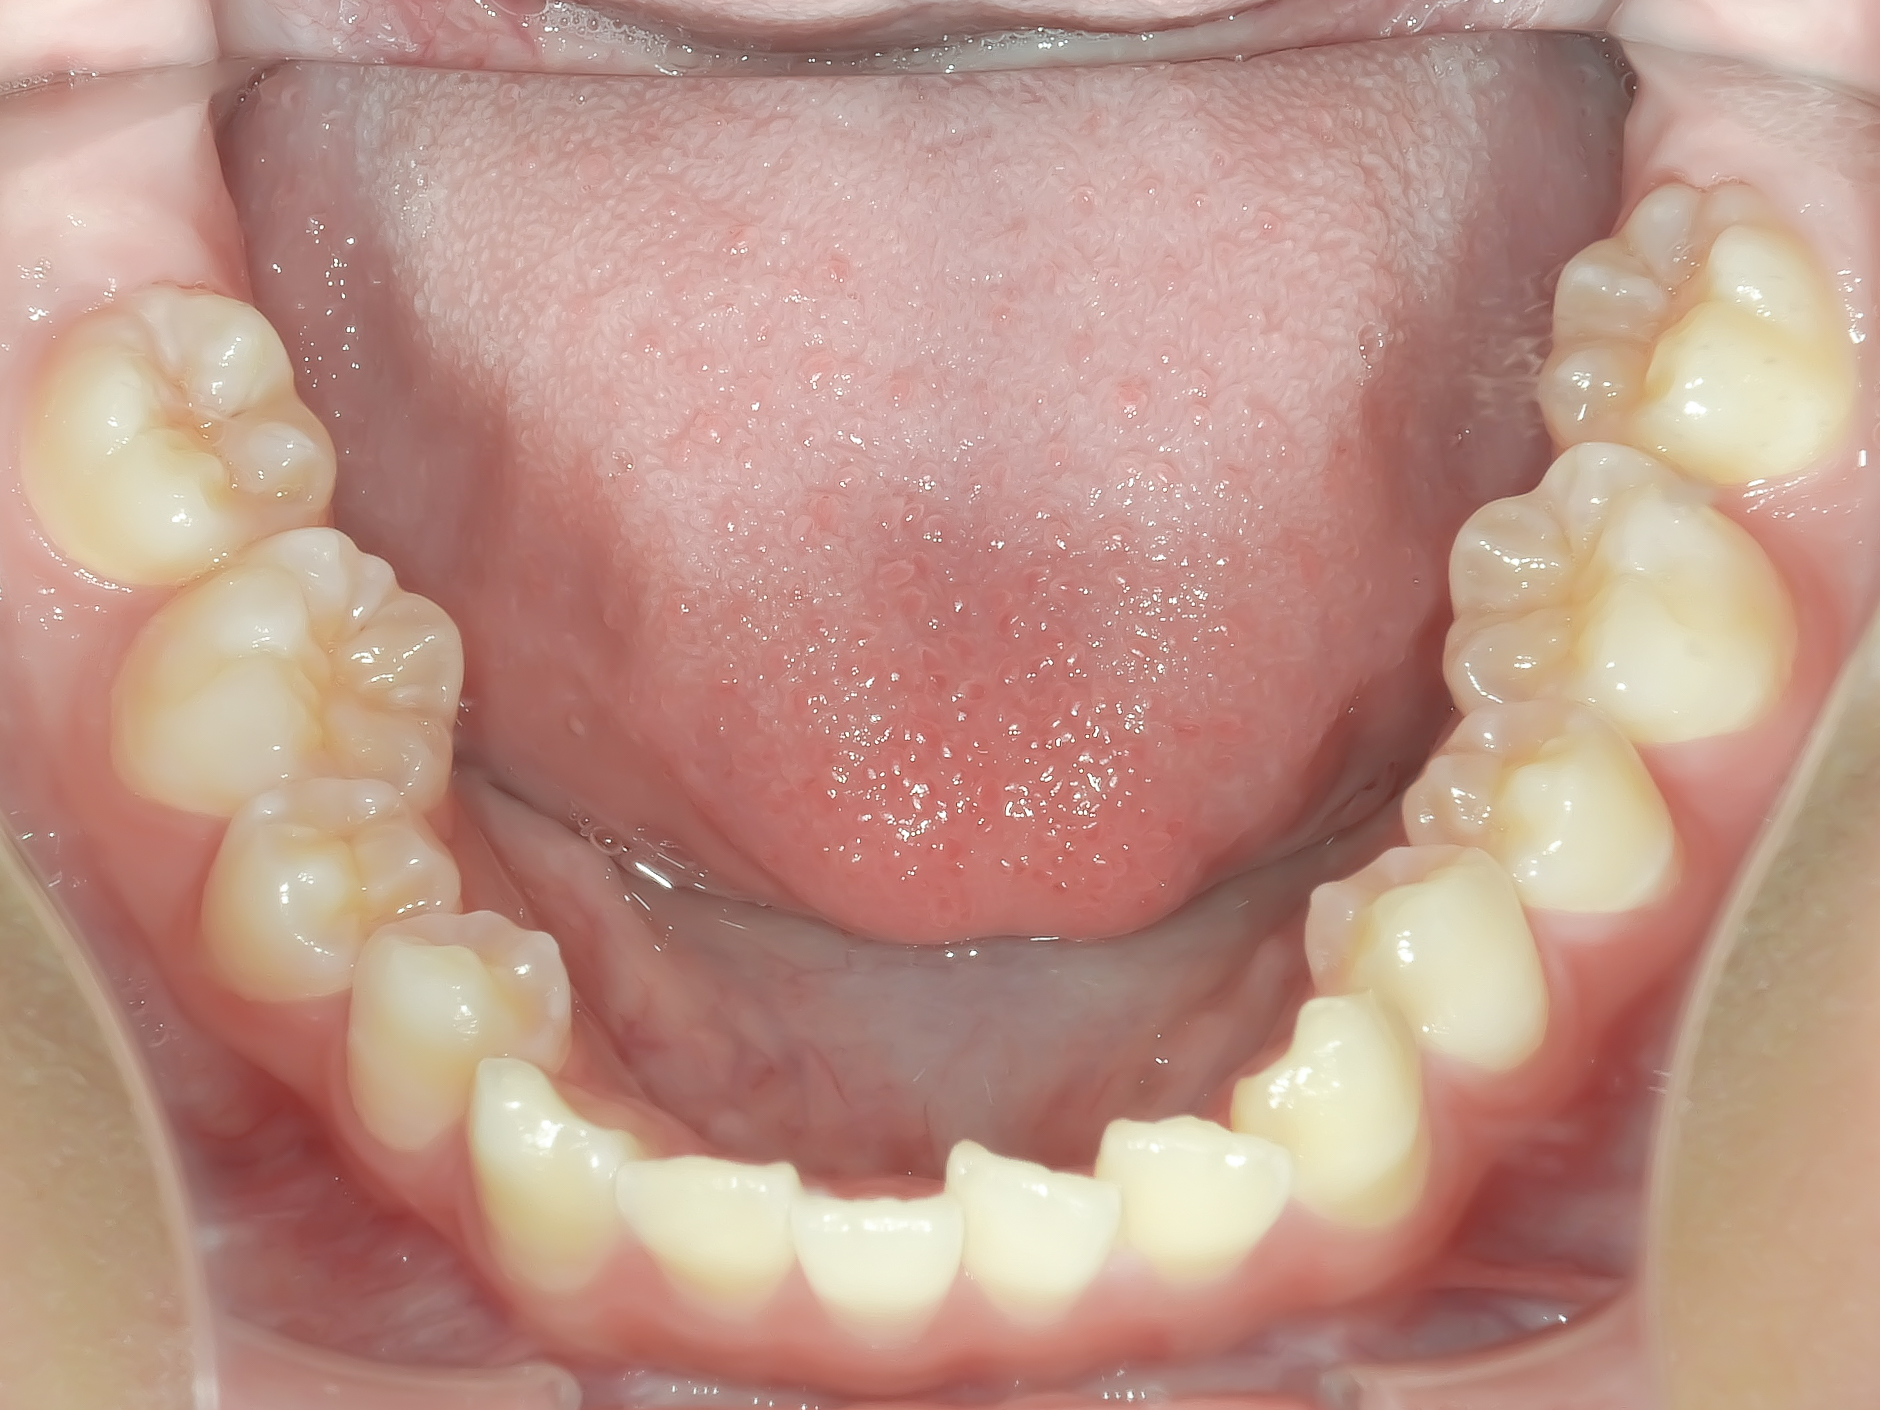

Before

下顎には軽度の叢生を認めます。